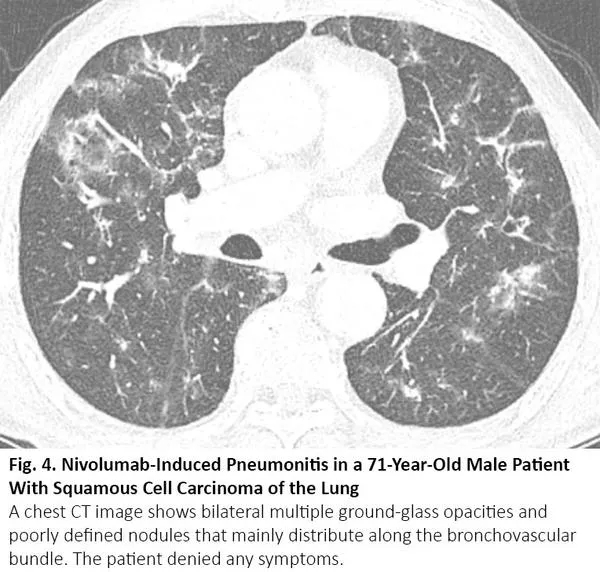

肺癌患者在病程中可能出现与COVID-19类似的CT异常,但这些异常是由于其他原因,如病毒性肺炎、癌症复发和间质性肺病。病毒性肺炎,特别是流感肺炎,在胸部CT上可表现为双侧磨玻璃样影和实性病变,胸部CT上位置分布相似10(图3),秋冬流感高发时,利用放射学检查结果来鉴别二者可能有问题。COVID-19 CT比流感肺炎CT更多见小叶间隔增厚及圆形阴影(典型肺周分布),但肺结节和树芽征相对更少。11

图3. 流感肺炎